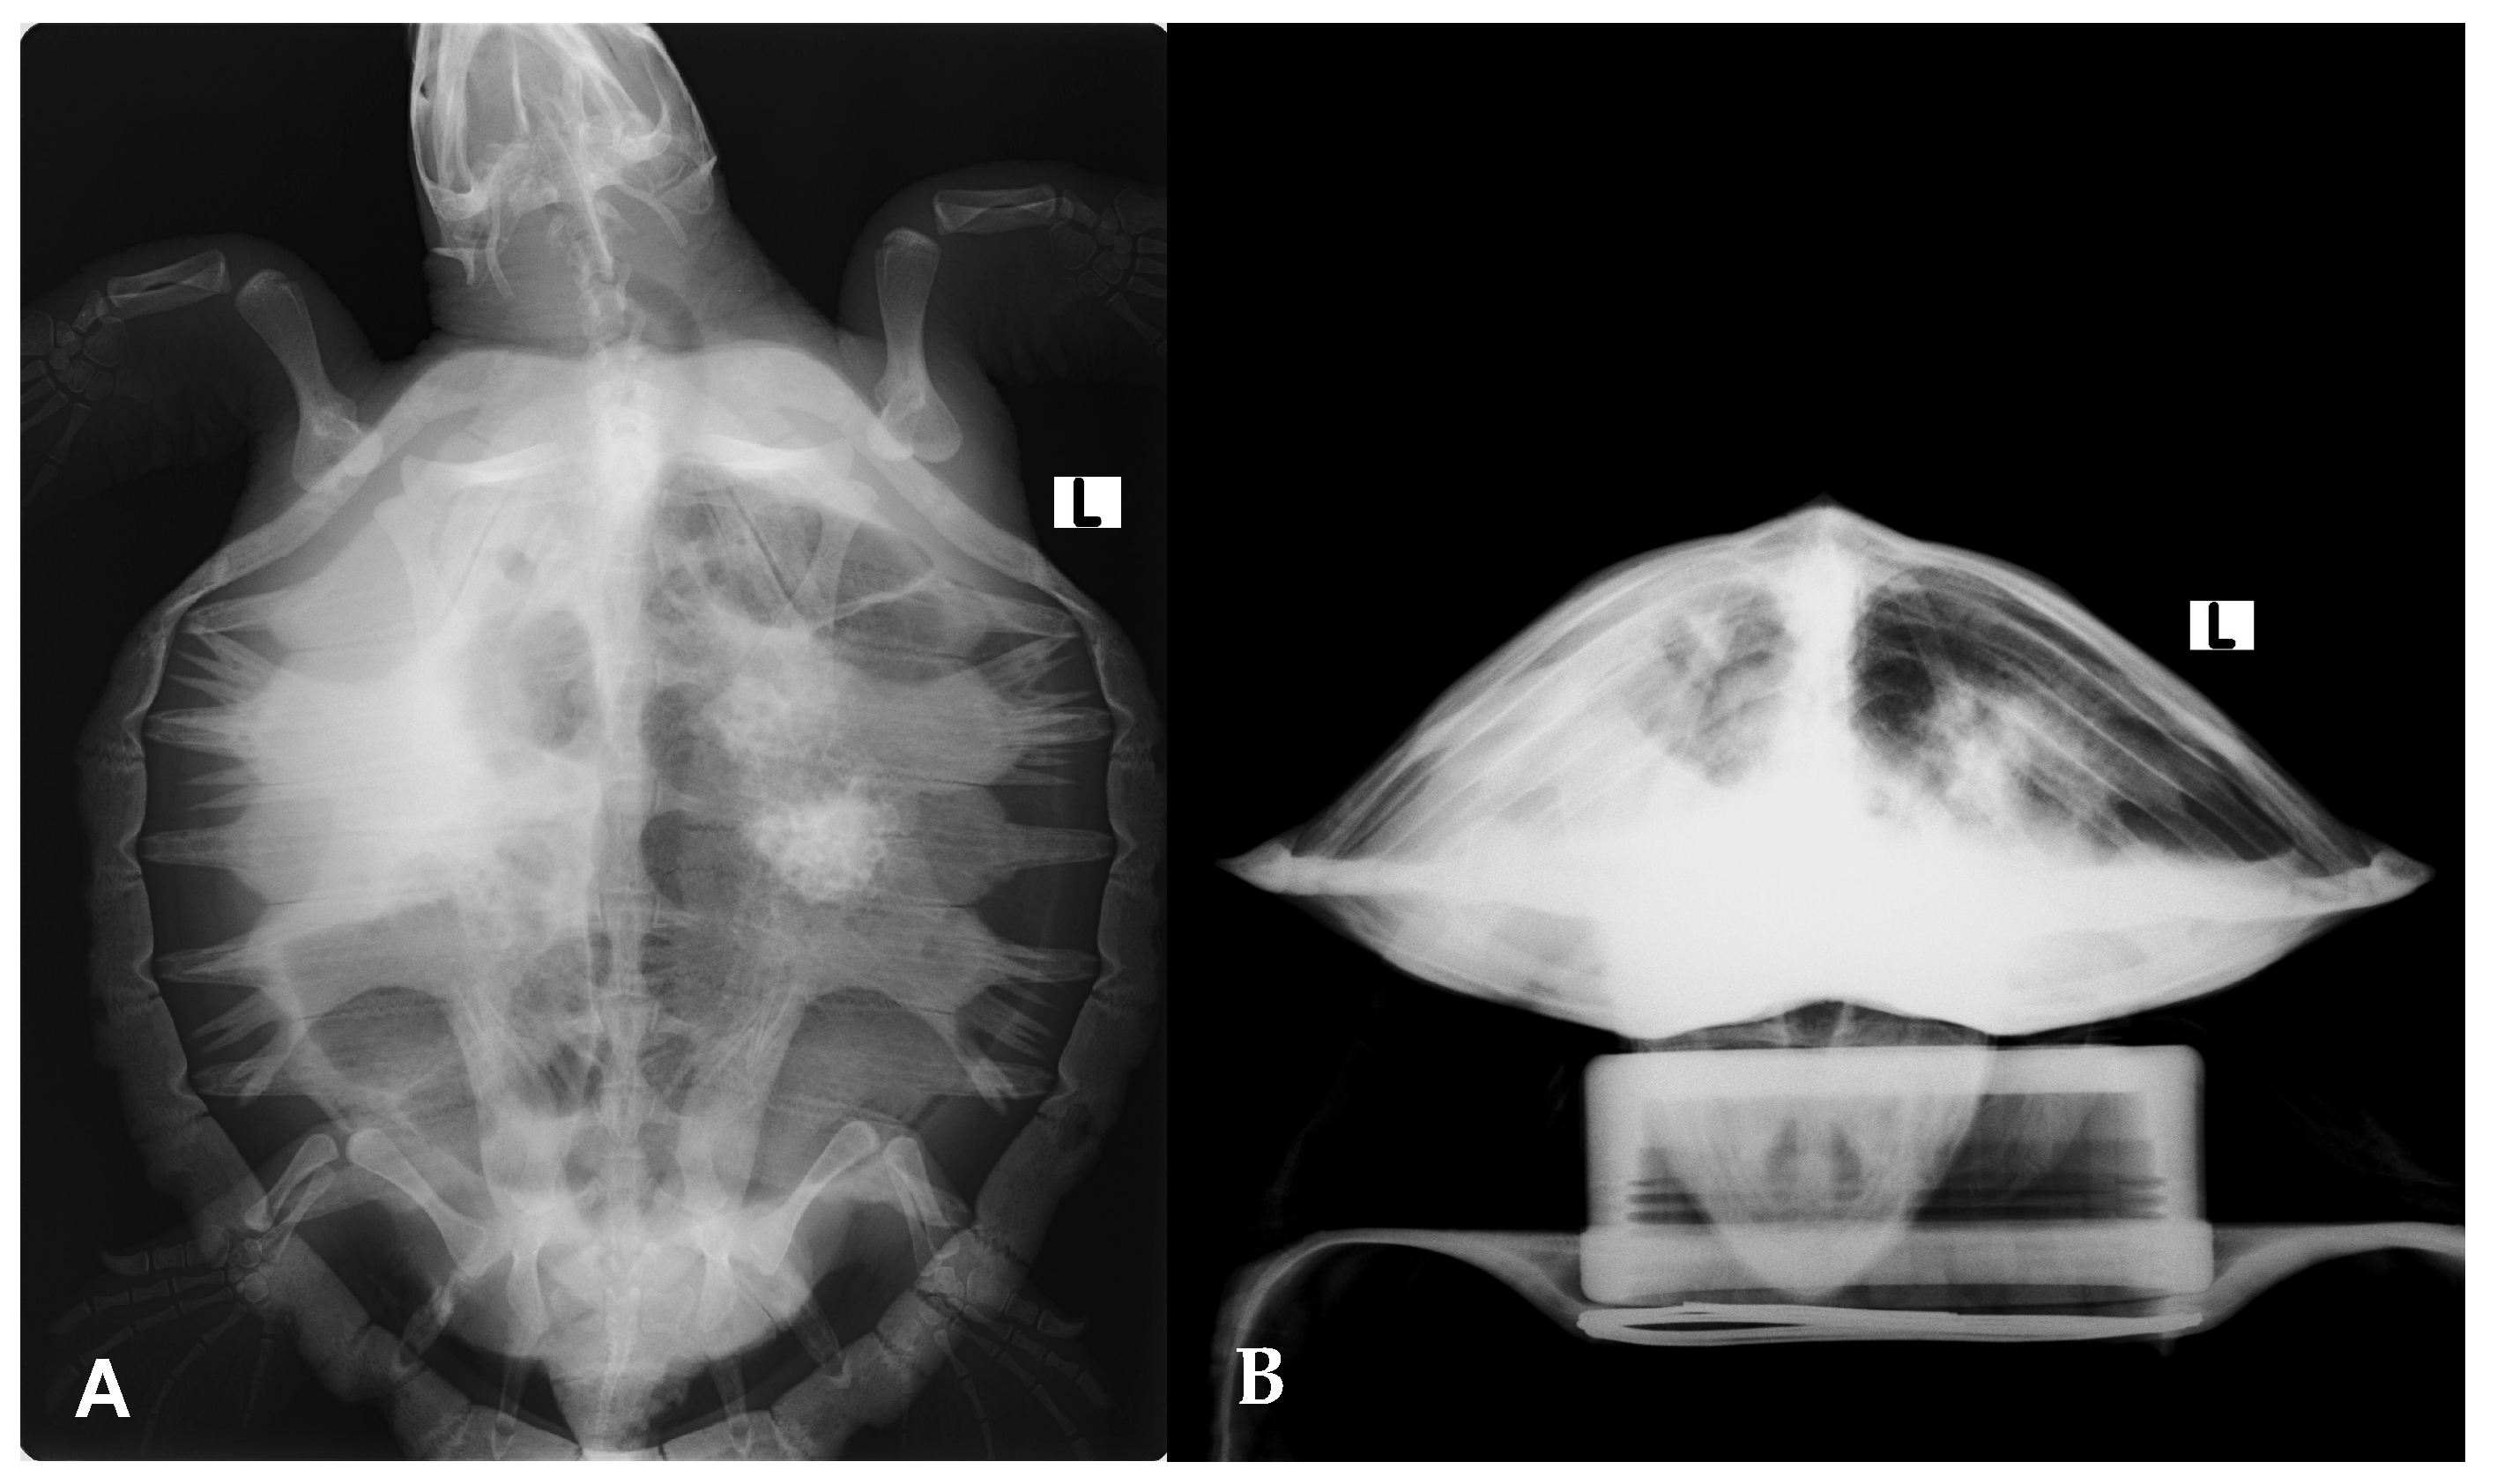

Radiographic evaluation showed diffuse increased pulmonary opacity, most pronounced in the right lung, along with ill-defined focal opacities in the left lung field (Figure 3). Microbiological cultures of the antemortem carapace lesions yielded Shewanella algae, Citrobacter gillenii, and Mucor spp.

Figure 3.

Radiographic evaluation of the Kemp’s ridley sea turtle (Lepidochelys kempii) shows increased pulmonary opacity, most pronounced in the right lung, along with ill-defined focal opacities in the left lung field. (A) Dorsoventral view; (B) craniocaudal view.

In this rescued individual, the entry route for B. bassiana remains speculative but likely involved the aspiration of contaminated seawater. This interpretation aligns with the findings of Stockman et al. (2013), who reported that pneumonia in cold-stunned Kemp’s ridley turtles may develop as a consequence of sea water aspiration [48]. Their study further noted a higher prevalence of unilateral pulmonary abnormalities in the right lung compared to the left [48]. When both lungs were affected, the right lung tended to show more severe lesions, consistent with the presentation in this rescued individual. Anatomically, the entrance to the right main bronchus in L. kempii is located ventral to the entrance to the left main bronchus at the tracheal bifurcation, a feature that likely predisposes the right lung to more easily accumulate sea water during aspiration, and therefore to more severe pneumonia [48].